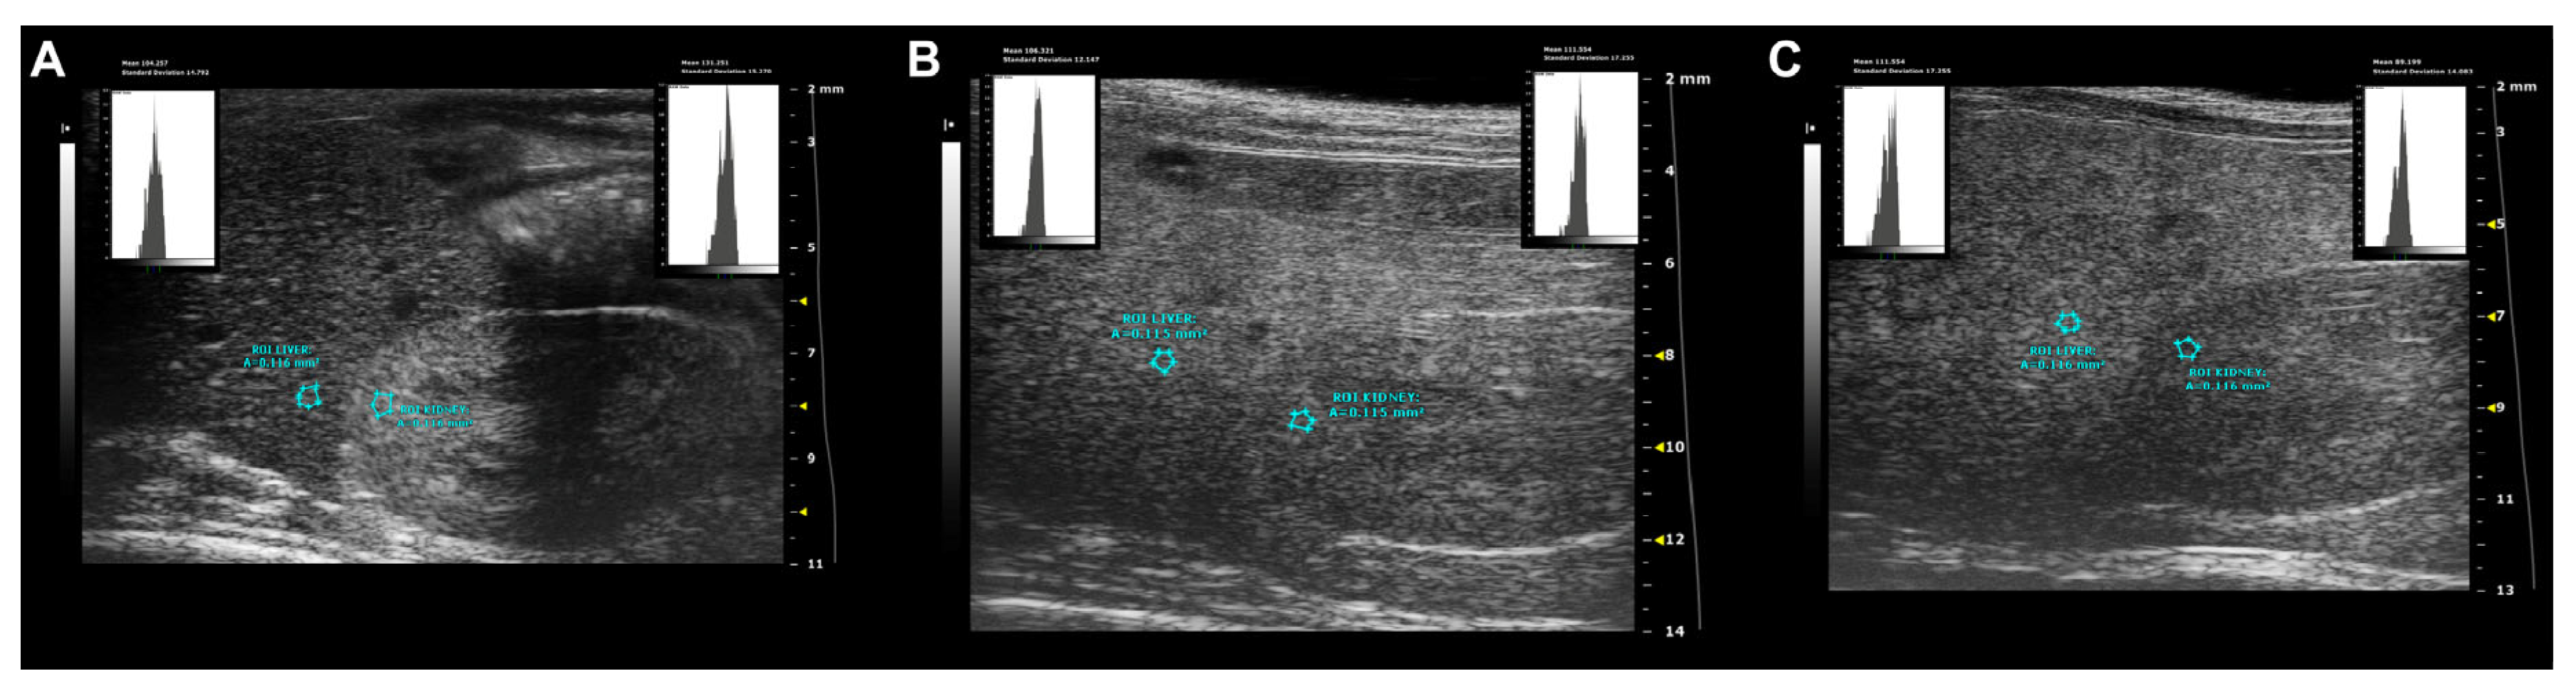

- Parametric analysis: Overall, normal hepatic parenchyma is less echogenic than the right renal cortex in rodents [7]. The hepatic echogenicity increases due to the presence of fatty infiltration and/or fibrosis, changing the relation between the liver and the right renal cortex [12].

- Hepatic-renal ratio (HR): A longitudinal view was acquired in order to have both the liver (caudate lobe) and the right kidney clearly visualized. Liver echogenicity was compared with that of the renal parenchyma, to normalize differences in the overall ultrasound gain value used for the acquisitions. A region of interest (ROI, (0.1 ± 0.02 mm2) was manually drawn and placed in the liver parenchyma, avoiding focal hypo- and hyperechogenicity. A second ROI was positioned in correspondence with a portion of the renal cortex devoid of large vessels along the focusing area of the image at the same distance from the probe to avoid distorting effects in ultrasonic wave patterns. HR values were obtained by dividing the mean grey level of the hepatic ROI for that obtained for the renal one (pixel intensity = average intensity/mm2, arbitrary units, a.u.) [9,44].

- Hepatic-portal vein ratio (HPV): Similarly, liver echogenicity was normalized to that corresponding to blood within the portal vein. Axial plane ultrasound images were acquired to visualize a portion of the portal vein in the center of the liver. One ROI (0.1 ± 0.02 mm2) was manually drawn and positioned within the lumen of the portal vein, while a second one was positioned in the liver parenchyma avoiding focal hypo- and hyperechogenicity, at the same depth and as close as possible to the center of the image, to maintain comparable ultrasound attenuation and avoid effects related to borderline echo distortion [9,44].

- Gray-level histogram analysis of echogenicity (GLH): Liver images at different scanning planes (left lateral lobe, longitudinal; caudate lobe, longitudinal; right median lobe, axial) were analyzed using a gray-level histogram to obtain the quantitative mean and standard deviation values of echogenicity of each spatial region. Anatomical landmarks (greater curvature of stomach; cranial pole of the right kidney; porta hepatis, at the level which aorta, portal vein, and caudal vena cava are visible in cross-section) were chosen to scan reproducible imaging planes. ROIs (1 ± 0.02 mm2) were manually drawn in the liver parenchyma, avoiding focal hypo- and hyperechogenicity and as close as possible to the center of the image. This approach includes more representative parts of the liver parenchyma and avoids distortion of image artifacts, with good intra-observer reproducibility [46]. Changes in brightness and variance of the liver parenchyma were reported as follows: mean echogenicity of different lobes; standard deviation of brightness within ROI encompassing right median lobe as measure of tissue heterogeneity; standard deviation of brightness among ROIs in all planes imaged as measures of anisotropy [46,47].

3.6. WD Causes Progressive Structural and Functional Changes in the Heart, Liver, and Kidney of C57Bl/6J Mice That Can Be Detected Early and Monitored In Vivo by HFUS